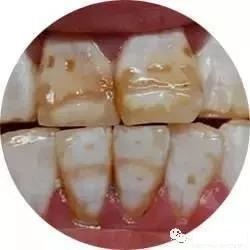

发育畸形

造成牙体缺损的发育畸形是指在牙发育和形成过程中出现形态、结构的异常。常见的造成牙体缺损的牙结构发育畸形包括釉质发育不全、牙本质发育不全、斑釉牙及四环素牙等。牙齿的形态发育畸形是发育过程中牙冠形态的异常,常见的有过小牙、锥形牙等。

釉质发育不全症轻者牙冠呈白玉色或褐色斑,严重者则出现牙冠形态不完整,釉质钙化不良,硬度降低,牙釉质表面粗糙且有色素沉着。

斑釉牙是在牙发育期间,由慢性氟中毒所致的牙体组织损害,牙冠表面出现白玉色或黄褐色斑块。

四环素牙又称四环素色素沉着,是在牙冠发育期间,由于受到四环素族药物的影响造成牙冠变色和釉质发育不全,牙冠呈灰褐色或青灰色,釉质透明度降低,失去光泽,严重者还可出现牙冠发育不全。